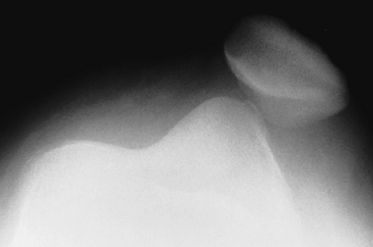

Fig 50. Patela bipartita.

A: Rx AP de rodilla. Fragmento supero-externo en la patela de bordes escleróticos, por variante bipartita.